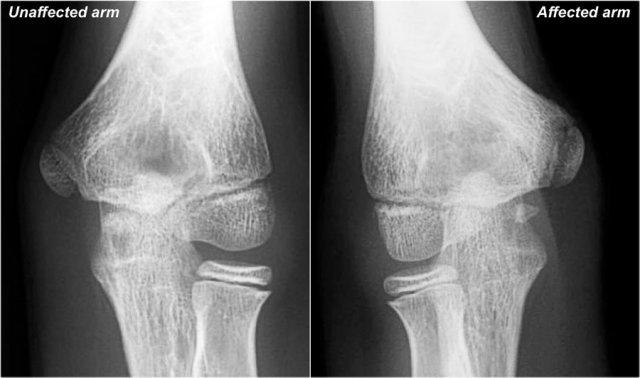

Little Leaguer’s Elbow

Đầu tiên hãy xem các hình ảnh của một bệnh nhân bị đau ở phía trong, sau đó tiếp tục đọc…

The findings are very subtle.

Mỏm trên lồi cầu trong của cánh tay bị ảnh hưởng có phần loãng xương hơn.

Trong những trường hợp này, chúng tôi thường yêu cầu chụp so sánh đối bên, vì sự khác biệt có thể rất tinh tế.

Chẩn đoán là khuỷu tay của vận động viên bóng chày nhí (Little Leaguer’s elbow), xảy ra do chấn thương stress mãn tính.

Vùng thấu quang trên phim X-quang, trông giống như một đĩa sụn tăng trưởng bị giãn rộng, là do sự phát triển xâm lấn của sụn vào vùng hành xương.

Trên MRI, bất thường rất rõ ràng.

Có phù tủy xương ở mỏm trên lồi cầu trong và cả ở xương lân cận (mũi tên vàng).

Khuỷu tay của cầu thủ bóng chày nhỏ tuổi còn được gọi là viêm mỏm xương chẩm giữa và một số người gọi là ly giải sụn tiếp hợp.

Nhân tiện, đây cũng có thể được gọi là gãy xương loại I theo Salter-Harris, nếu đây là một chấn thương cấp tính.

Notice the normal ulnar collateral ligament (red arrow).

Ở trẻ em, điểm yếu trong stress valgus không phải là dây chằng bên trụ mà là sụn tiếp hợp.

Bệnh nhân này lớn tuổi hơn một chút.

Mỏm trên lồi cầu bên trái đã liền sụn, nhưng bên phải sụn tiếp hợp vẫn còn hở một chút.

On the MR there is marrow edema.

Lưu ý rằng cũng có một số phù nề tại vị trí bám của dây chằng bên trụ, vì vậy cũng có một số rách của dây chằng bên trụ (UCL).